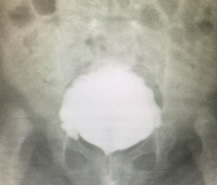

A 12 Fr umbilicus catheter was inserted by the ureter into the bladder like urinary drainage and ferulization for three weeks (Figure 4). The child was started on oral liquid feeds within 4 hours that had been suspended for an abdominal distended. The catheter was removed after ensuring that the patient and family could catheterize every 3 hours without difficulty previous a control cistograma (Figure 5 and Figure 6).

Figure 5. . Control cistograma.